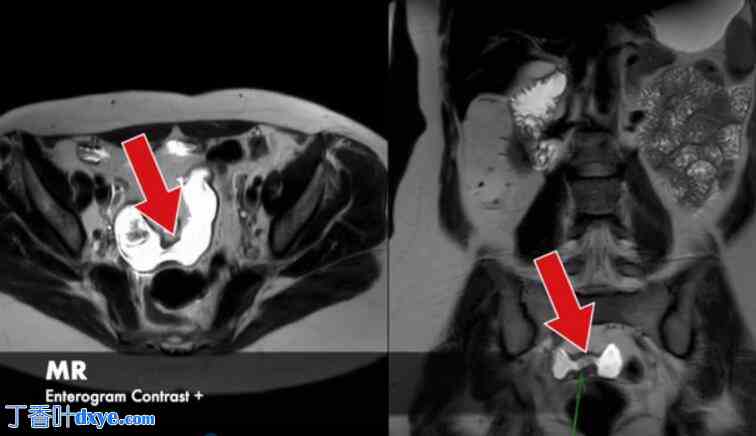

41岁女性,长期腹痛、恶心和呕吐

背景:6年前确诊为克罗恩病,多种治疗均无效。无肠外表现。

检查:

-CT:回肠末端和小肠壁增厚

·结肠镜检查:回肠远端狭窄延伸至回盲瓣·磁共振成像(MRE):回肠远端两处纤维化狭窄。无穿透性病变。

治疗史:诊断时最初使用甲氨蝶呤,后停用。目前每日服用硫唑嘌呤75毫克,每日服用布地奈德3毫克。

计划:小肠切除术和Kono-s吻合术

磁共振肠造影对比剂 +